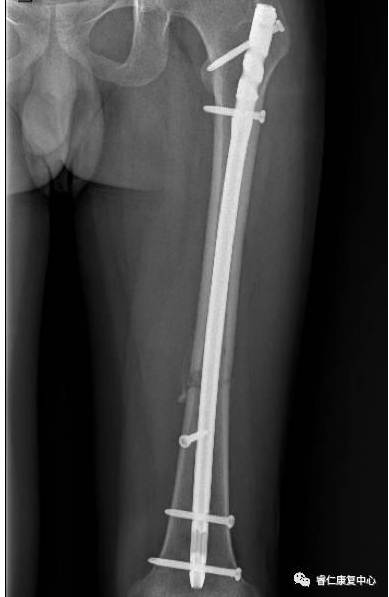

胡大教授讲解大腿骨折术后功能锻炼